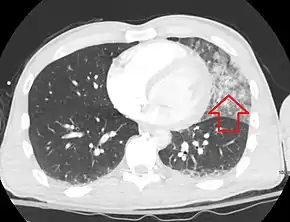

A CT scan showing a pulmonary contusion (red arrow) accompanied by a rib fracture (blue arrow) | |

Computed tomography

Computed tomography (CT scanning) is a more sensitive test for pulmonary contusion,[3][32] and it can identify abdominal, chest, or other injuries that accompany the contusion.[37] In one study, chest X-ray detected pulmonary contusions in 16.3% of people with serious blunt trauma, while CT detected them in 31.2% of the same people.[45] Unlike X-ray, CT scanning can detect the contusion almost immediately after the injury.[42] However, in both X-ray and CT a contusion may become more visible over the first 24–48 hours after trauma as bleeding and edema into lung tissues progress.[46] CT scanning also helps determine the size of a contusion, which is useful in determining whether a patient needs mechanical ventilation; a larger volume of contused lung on CT scan is associated with an increased likelihood that ventilation will be needed.[42] CT scans also help differentiate between contusion and pulmonary hematoma, which may be difficult to tell apart otherwise.[47] However, pulmonary contusions that are visible on CT but not chest X-ray are usually not severe enough to affect outcome or treatment.[36]